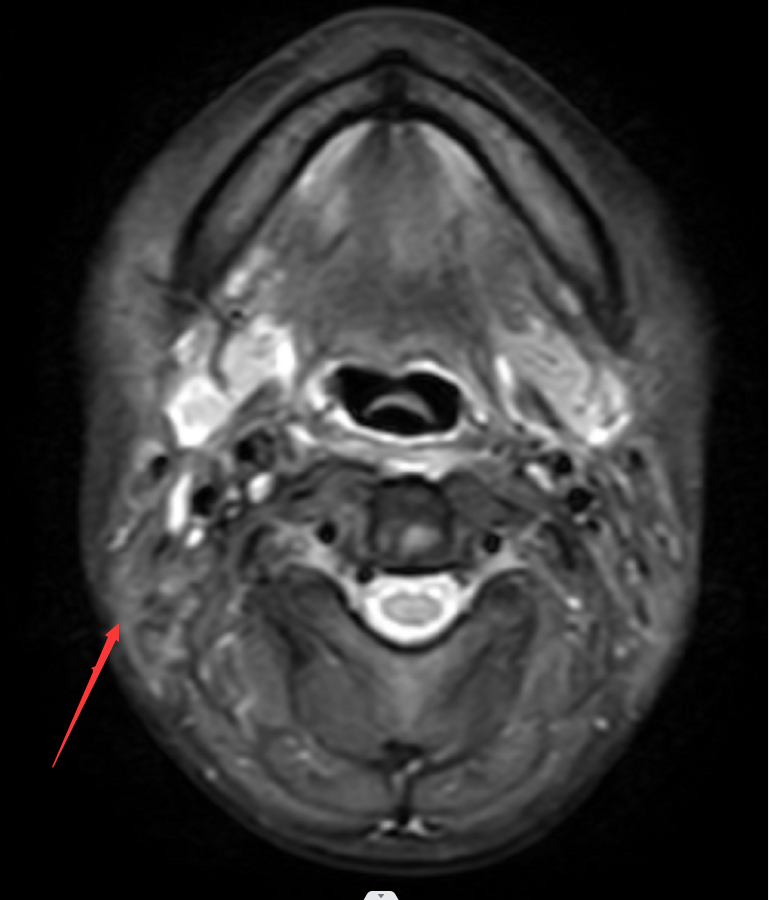

(射波刀治疗后10天,患者右颈部肿瘤已较前明显缩小,局部疼痛明显减轻。射波刀治疗后2月复查MRI提示右颈部淋巴结已消失)。进展后继续化疗加中药巩固治疗,小萍整个治疗过程,均长期配合中医药辨证治疗。此阶段的小萍情况明显好转,可生活自理,住院期间无需陪人照料,饮食、睡眠基本恢复正常。颈部肿块消失,疼痛明显缓解,无需止痛药治疗。

2020-12-18射波刀治疗后